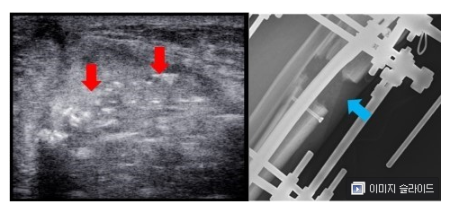

프리사이스2는 속성연장술과 달리 외고정장치를 사용하지 않고 내고정장치만을 사용하여 수술을 진행합니다.

하지만 뼈 자체만을 고정하여 연장을 진행하기 때문에 주변 조직이 연장 속도를 따라가지 못해 까치발과 같은 부작용이 발생할 수 있으며, 연장 중 체중 부하가 어려워 휠체어 등의 보조적인 장비의 도움이 필요합니다.